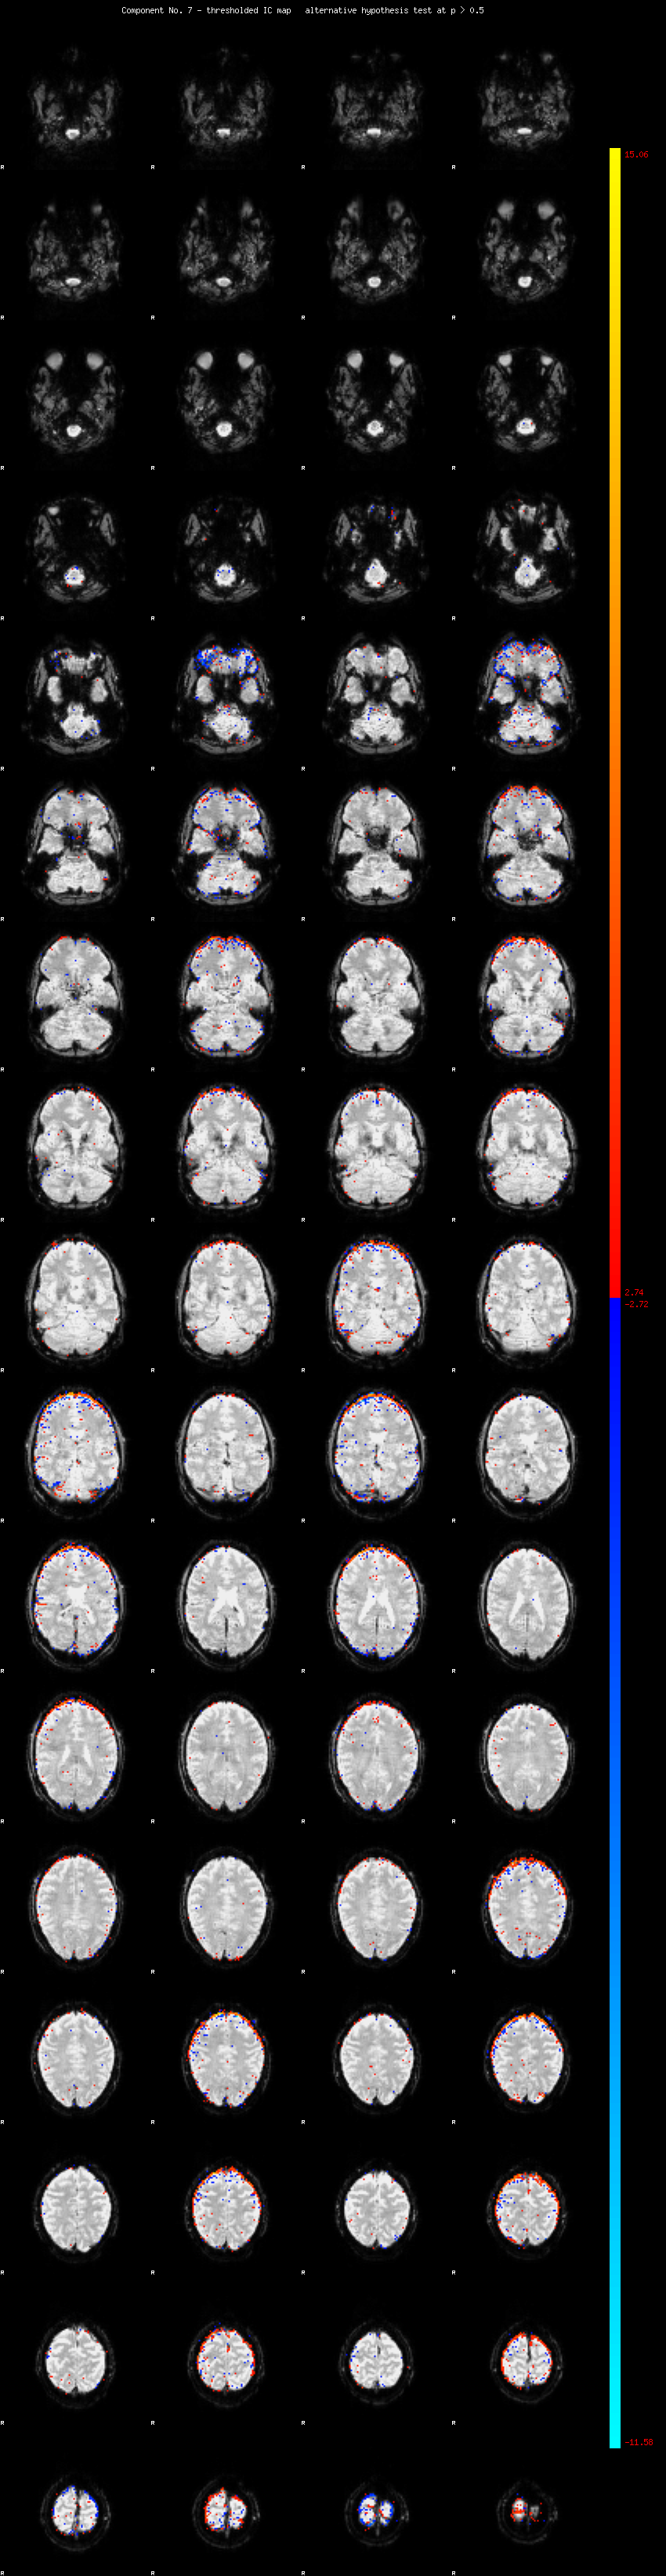

MELODIC Component 7

2.22 % of explained variance;     1.47 % of total variance

MMfit